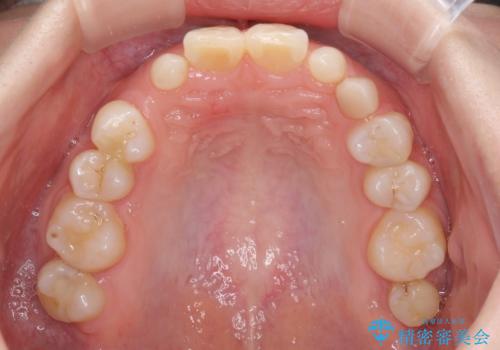

欠損と残存乳歯 矯正治療とインプラント治療

- 残存した乳歯や歯の欠損、歯並びを気にして来院された患者様です。

乳歯を残した状態は予後がよくないこと、矯正治療と補綴治療を総合的に進めていきたいとのことで、インビザラインによる矯正治療とインプラント補綴治療を並行して進めていくこととしました。